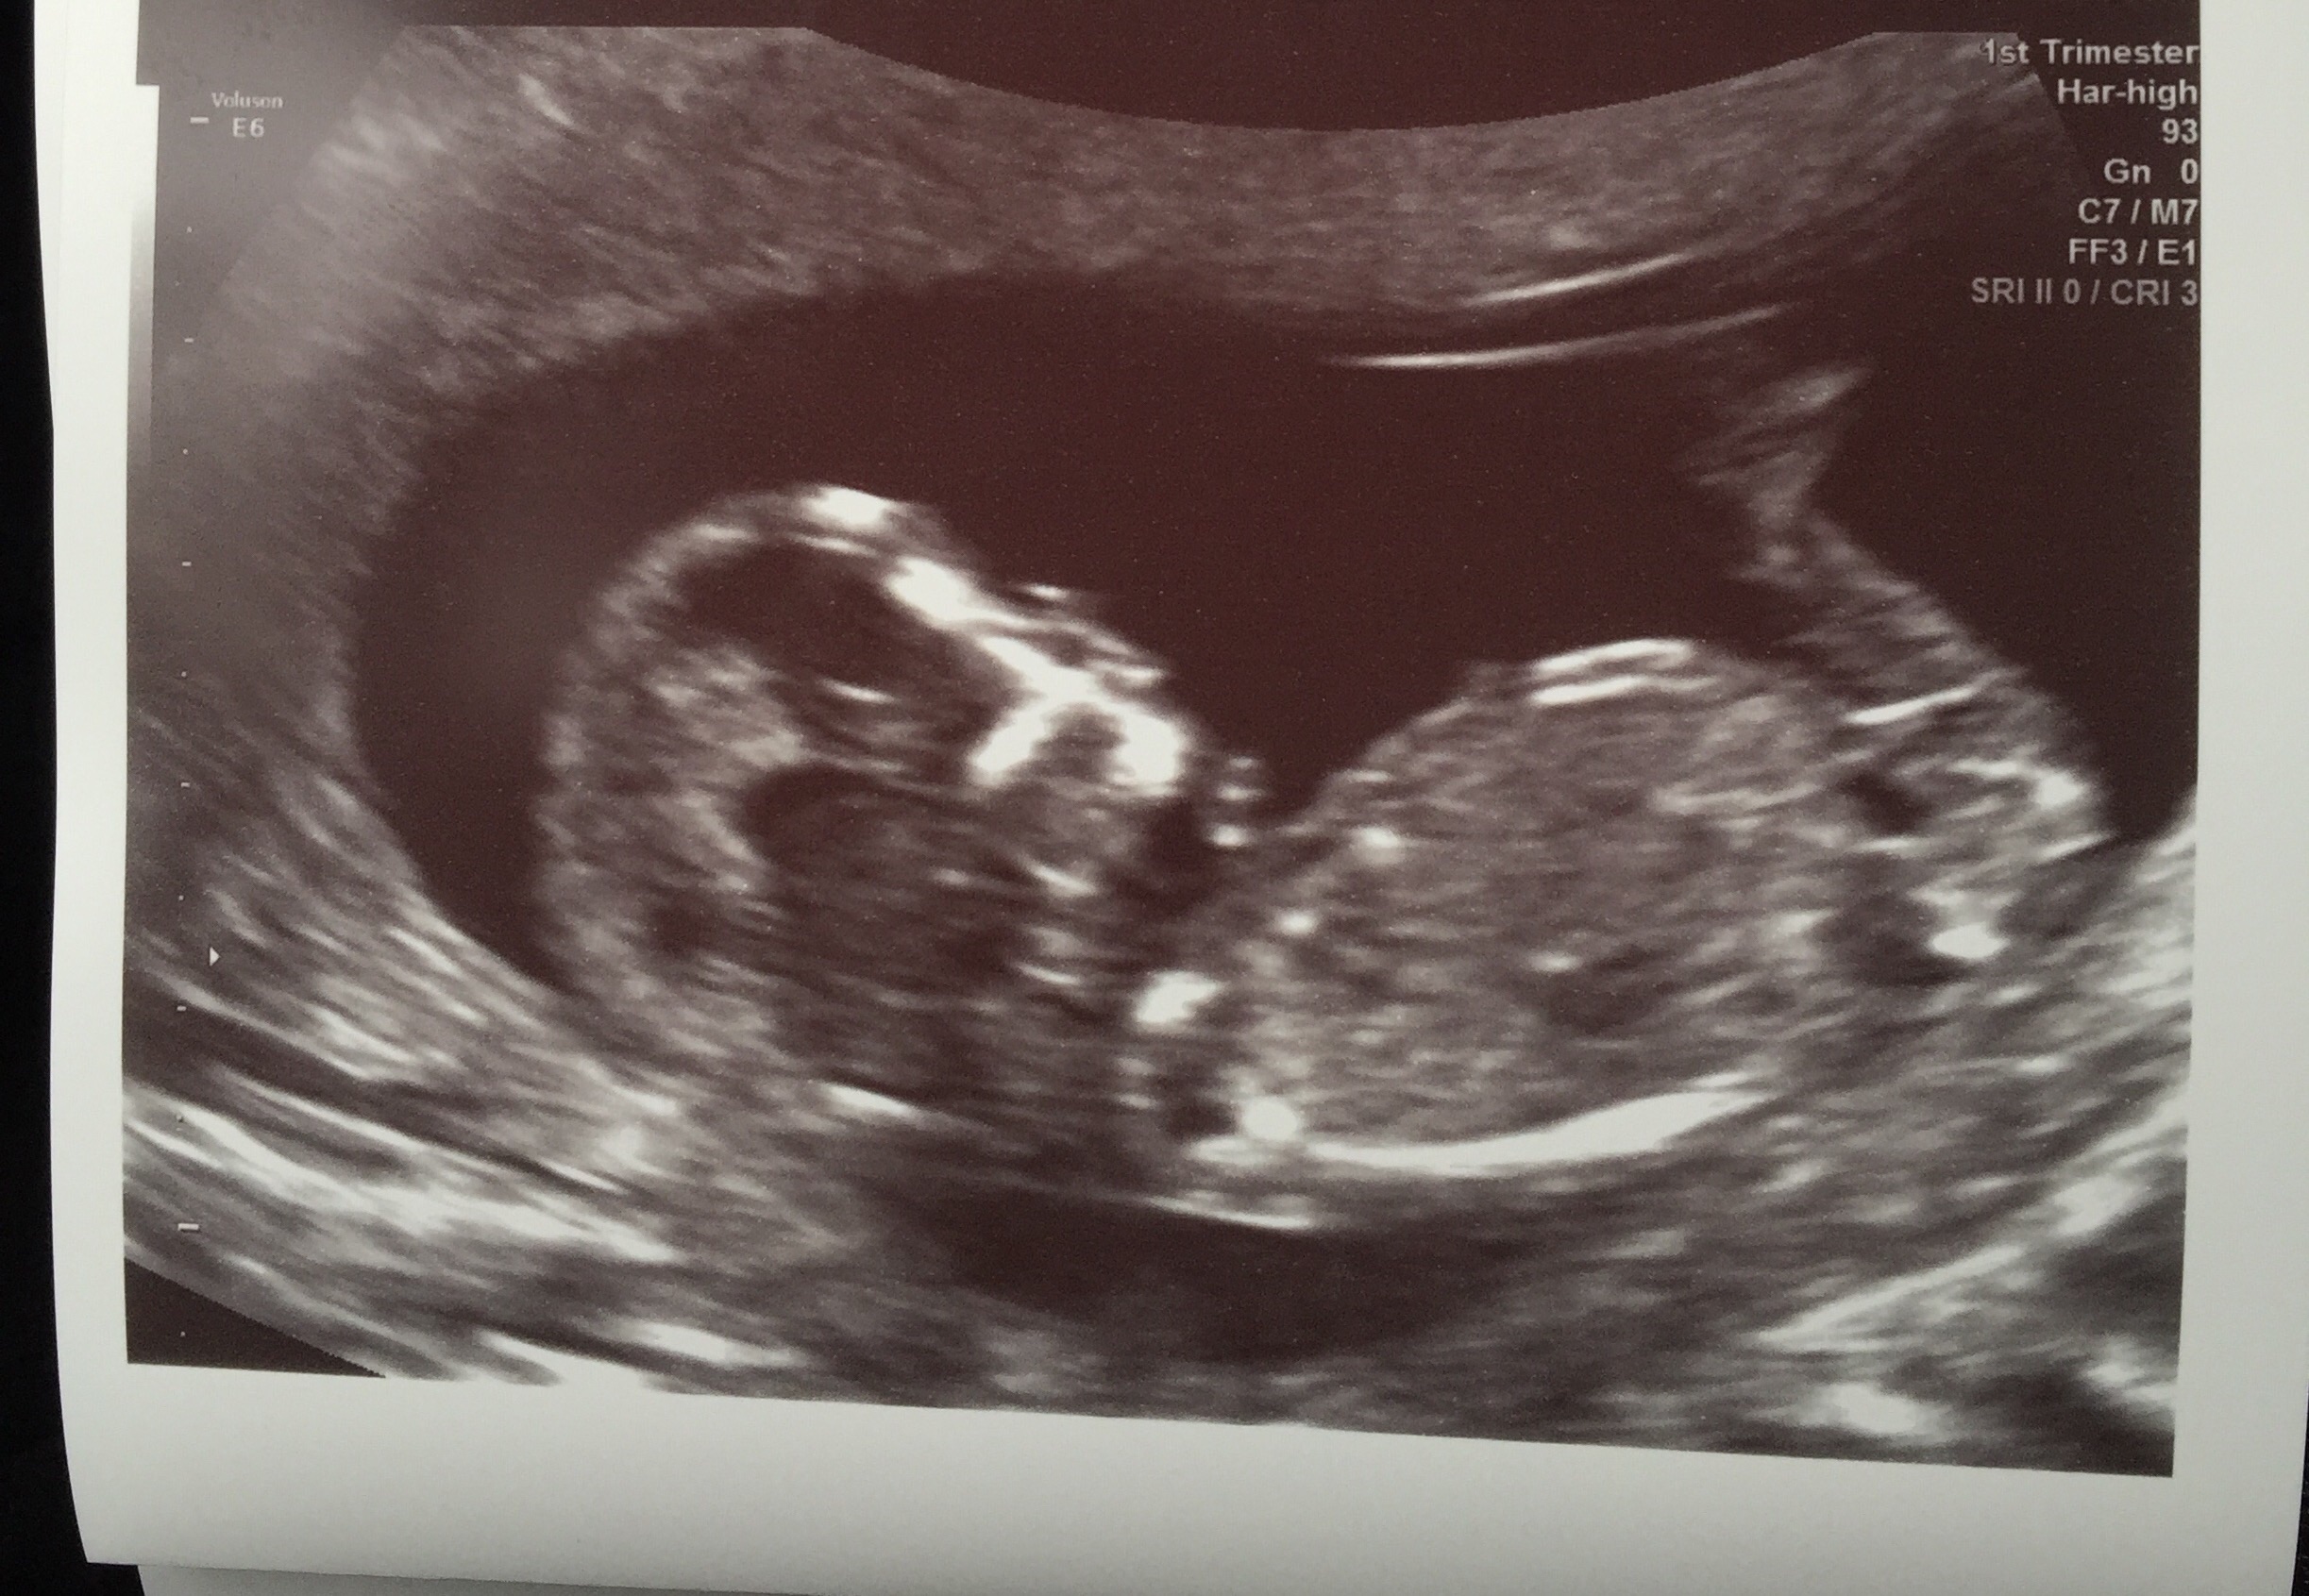

I'm desperate to know, any guesses it looks boyish to me

Boy lean from first one

Leaning boy, good luck

Thank you for guessing, the first photo had me thinking boy...

Boy guess on first photo but then second looks girly....